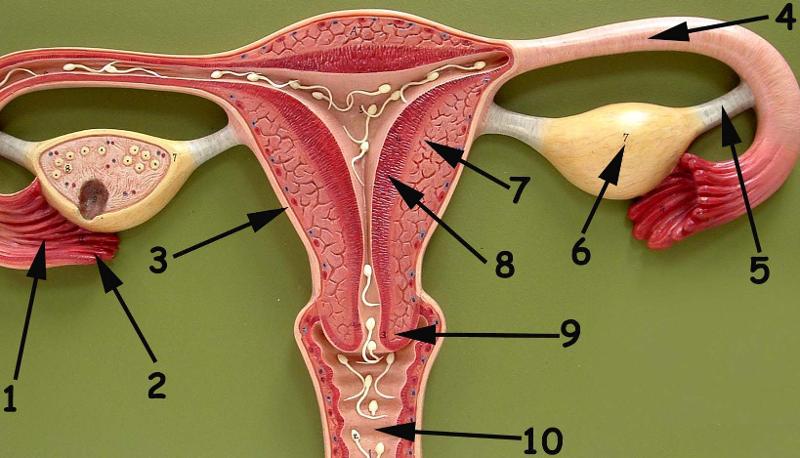

Broad ligament

Cervix

Corpus luteum

Endometrium

Fimbriae

Mature (=Graafian, = antral) follicle

Myometrium

Overian ligament

Ovary

Perimetrium

Primordial/primary/secondary follicle

Round ligament (of uterus)

Uterine (=fallopian) tube

Uterus

Vagina

Vaginal orifice